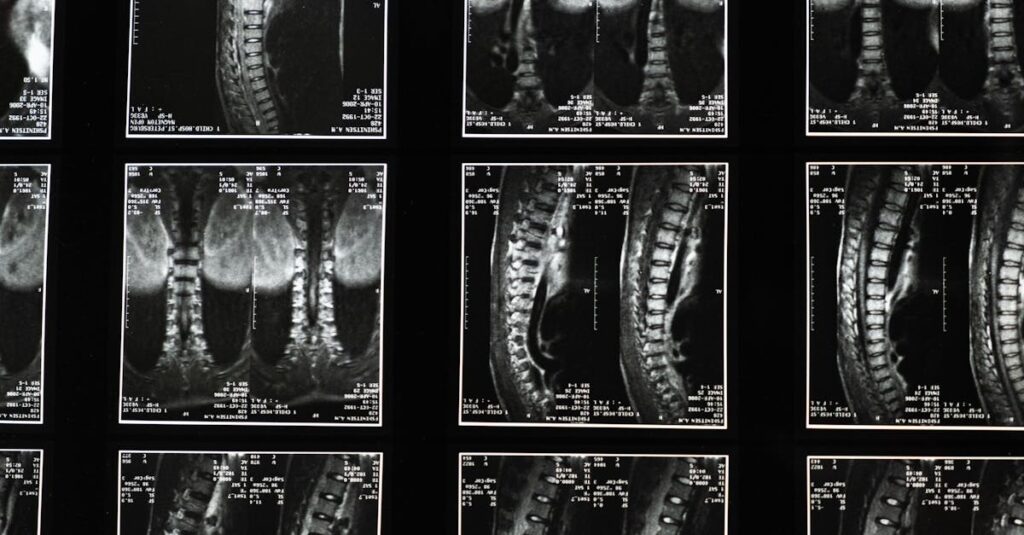

Patients in Saint-Jérôme are encouraged to undergo detailed evaluations, including MRI and CT scans, to confirm the extent and nature of disc herniation. Dr. Sylvain Desforges employs a comprehensive assessment protocol at the DiscRelief Clinic, leveraging advanced imaging coupled with clinical expertise to map precise nerve involvement and tailor patient-centric strategies.